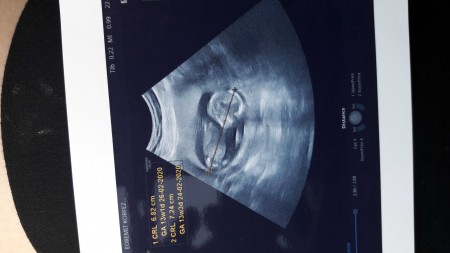

Kızlar cinsiyet tahmini alabilir miyim? 15.haftadayız ama ufaklık kendini göstermiyor. Genelde hep yüzüstü yatıyor.

Kapatılma nedeni: Cinsiyet tahmini için gebelik dışı sohbetten yardim alabilirsiniz. Anlayisiniz icin tesekkurler

Bana erkek gibi geldi canım:)çok benzettim

Koca kafalı gibi erkek derler böyle olunca. Ama Dr daha iyi bilir tabi..